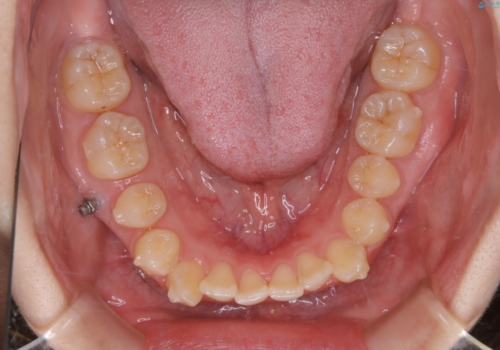

- 非抜歯、インビザライン治療希望の患者様です。

右の犬歯が八重歯になっており、通常であれば抜歯を選択する可能性が高くなりますが、

マイクロインプラントと呼ばれる骨に打ち込むネジを使用し、非抜歯での治療計画を立てました。

マイクロインプラントを使用することで非抜歯での治療が可能となりました。

マイクロインプラントを使用せずに無理に非抜歯治療を行った場合、

治療後に出っ歯になってしまうなどの問題が起きる可能性が高いです。